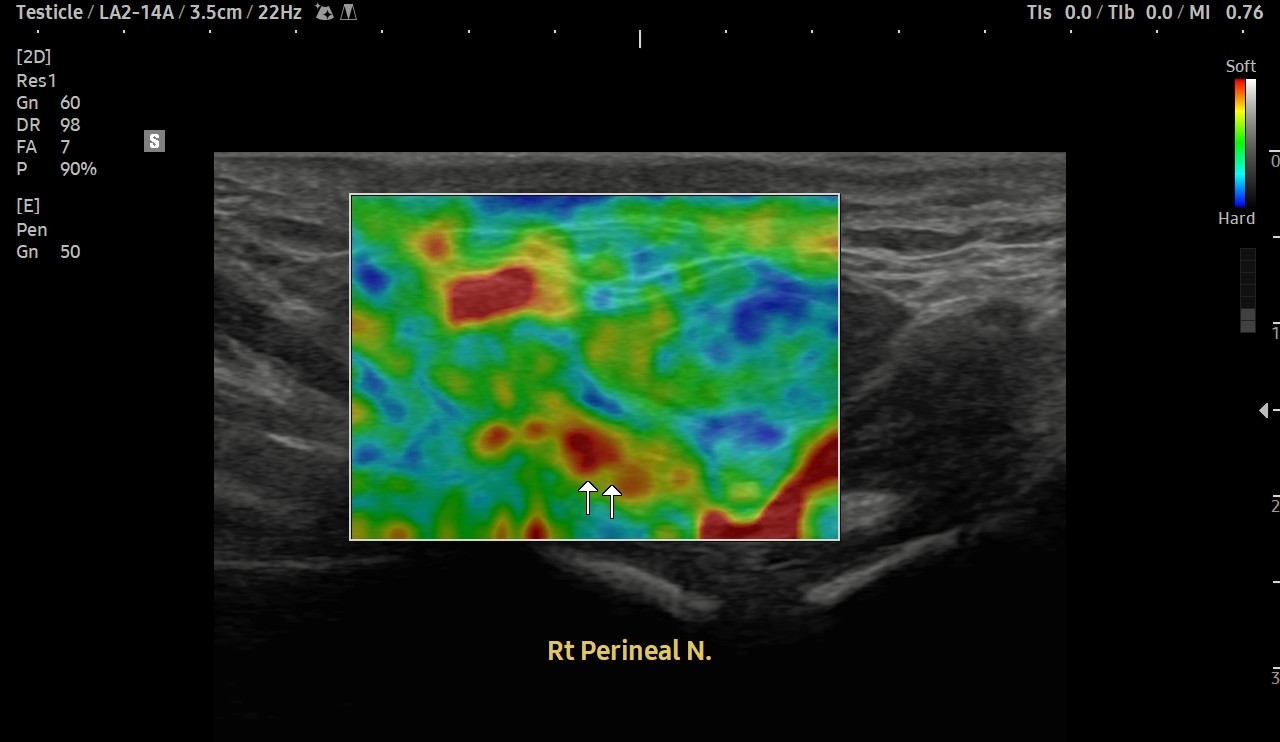

[치료 전]

[치료 후]

- 치료횟수 : 20 회